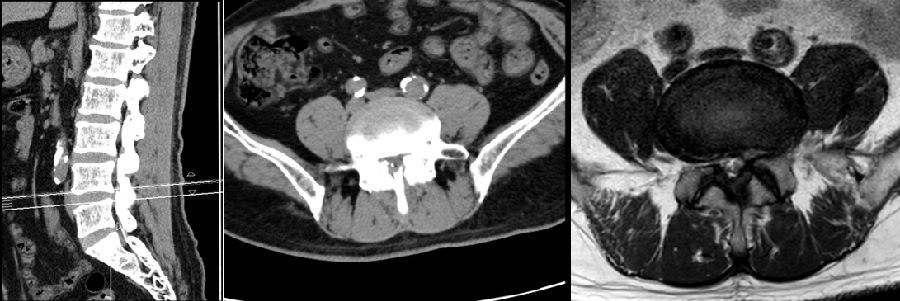

病例

男,64岁。

主诉:腰痛2年、加重伴左下肢疼痛麻木4个月,左小腿后外侧为著。

术后复查

思考和建议:

术前停用抗凝药

术中彻底止血(特别是骨面的出血)

尽量减少骨性结构破坏

放置引流管

避免水压过大(<30mmHg)

一旦出现神经症状,尽早手术(12小时内)